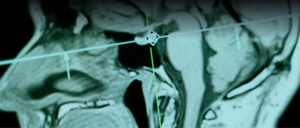

Neurocirurgia

Pessoas diagnosticadas ou com suspeita de aneurismas, malformações arteriovenosas (MAVs) e acidentes vasculares cerebrais (AVCs), que precisam de avaliação detalhada e possíveis intervenções cirúrgicas.

Dr. Everson Akio Sakô

Neurocirurgia é a área da neurocirurgia dedicada ao manejo de doenças vasculares do sistema nervoso central. Através de técnicas modernas, como procedimentos endovasculares e cirurgias